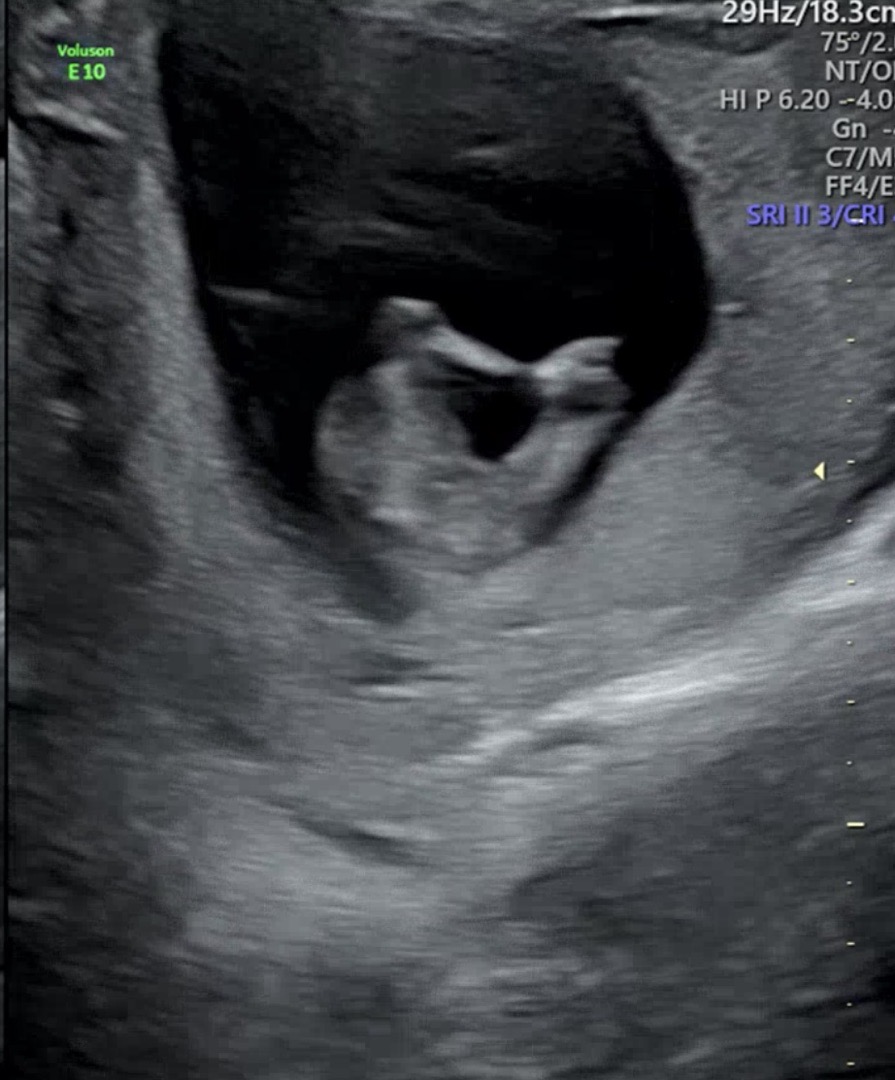

12주 초음파 성별 궁금해요!!

오늘 12주 5일차 초기정밀초음파를 보고 왔어요!! 아가가 너무 많이 움직여서 각도법으로 보기 어렵더라구요ㅠㅠ 그나마 양반다리하고 있는 다리사이가 찍혔는데 과연 성별은 뭘까요??